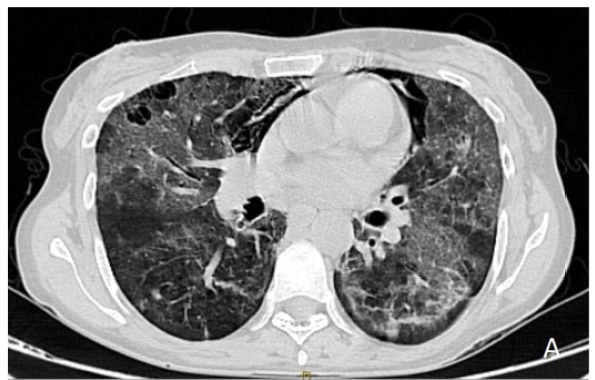

Pneumocystis Pneumonia Complicated by Pneumomediastinum in HIV Patient

Yassine Zerhari, Asaad El Bakkari, Hatim Essaber, Soukaina Allioui, Hounayda Jerguigue, Youssef Omor and Rachid Latib. 12(4): 01-03.